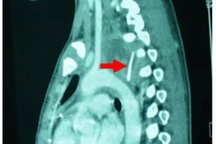

Tại đây, bệnh nhân được chỉ định nội soi và chụp phim CT.scan ngực. Kết quả cho thấy dị vật là miếng xương gà nằm ngang quai động mạch chủ ngực đe doạ gây thủng động mạch này. Sau đó bệnh nhân được chỉ định soi gắp lấy dị vật tại phòng mổ dưới sự hỗ trợ của bác sỹ gây mê hồi sức.

Ê-kíp phẫu thuật tiến hành mở lồng ngực trái và phát hiện mảnh xương gà dài 3cm, có cạnh sắc bén, còn dính đầy thịt (khoảng 20 gram) đâm thủng thực quản và phế quản góc bên trái, xuất hiện tràn khí trung thất trên và trung thất bắt đầu có dấu hiệu áp xe. Các bác sỹ nhanh chóng lấy mảnh xương gà ra và khâu lại đường rách của phế quản và thực quản, dùng dung dịch sát khuẩn rửa sạch phẫu trường trước khi đóng thành ngực.